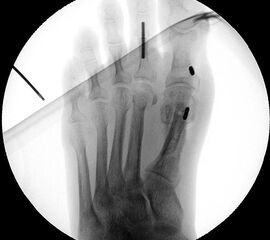

Die dorsoplantaren Röntgenaufnahmen zeigen eine Open-wedge Technik mit der normalerweise ein erhöhter intermetatarsaler Winkel gut zu korrigieren ist (Abbildung 3). Die Wirksamkeit einer Basisosteotomie ist umso größer, je proximaler diese durchgeführt wird. Je weiter distal die Osteotomie, umso geringer die Korrektur. Auf den postoperativen Bildern ist der distal unverändert große Abstand zwischen Metatarsale I und Metatarsale II erkennbar, bei gleichzeitiger Subluxation des Großzehengrundgelenks und dezentrierten Sesambeinen. Darüber hinaus finden sich initiale degenerative Veränderungen im Großzehengrundgelenk. Klinisch bestand eine hohe Weichteilspannung, bei verkürzter Extensor- und Flexor hallucis longus Sehne.  Daher wurde ein verkürzendes Verfahren zur Revision gewählt (Abbildung 4). Die Lapidusarthrodese stellt ein sehr zuverlässiges Verfahren zur Behandlung von Hallux valgus Rezidiven dar 9. Die Fusion des Tarsometatarsale-I-Gelenks kombiniert Stabilität mit einem hohen Korrekturpotenzial. Aufgrund der verfahrensimmanenten Verkürzung des ersten Strahls und der in diesem Fall bereits präoperativ vorhandenen Transfermetatarsalgie wurde die Entscheidung für eine verkürzte Weil-Osteotomie am zweiten bis fünften Strahl gefällt. Die Kombination beider Verfahren führte zu einem homogenen Metatarsale-Index und zu einer gleichmäßigen plantaren Druckverteilung 10. Die Hallux valgus interphalangeus Fehlstellung wurde mit einer Akin-Osteotomie korrigiert.